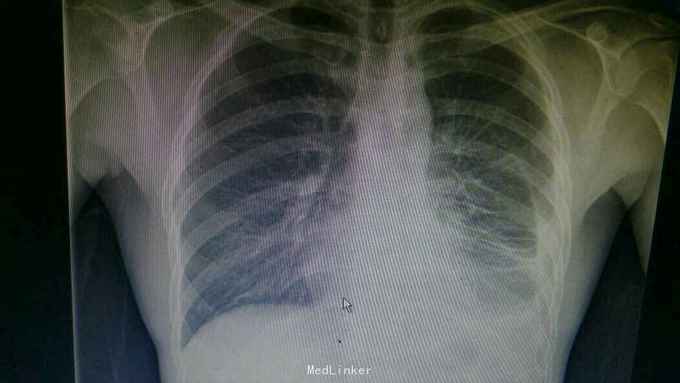

主诉:反复咳嗽、气促1周。 病史:患者1周前无明显诱因出现咳嗽、气促,无寒战畏寒,无盗汗乏力,无头痛头晕,无鼻塞流涕,遂就诊我院。

查体:生命体征平稳。左侧胸部叩诊浊音,左肺呼吸音低,右费呼吸音清。 辅查:胸片:左侧大量胸腔积液。胸水检查:淋巴细胞为主,胸水蛋白:52.4g/l。T-SPOT-A15个,B 10个。

诊断:结核性胸膜炎。 治疗:入院予以胸腔引流术持续引流胸水,排除乙肝及真菌感染后,予以四联抗结核治疗后复查胸片,左侧少量胸腔积液,予以拔出引流管。